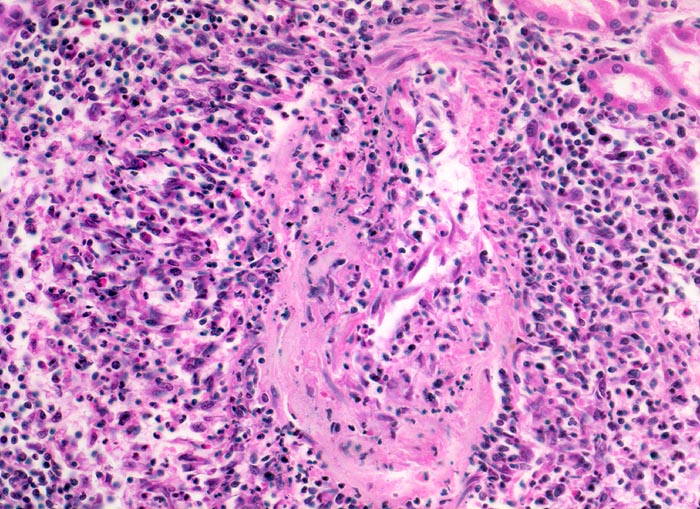

Staats/ Polyarteriitis nodosa Makroform

Polyarteriitis nodosa Makroform

Morphologische Merkmale:

• Unauffällige Glomerula.

• Grössere intrarenale Arterien mit teils zirkulären, teils segmentalen, transmuralen fibrinoiden Gefässwandnekrosen und gemischtem transmuralem Entzündungsinfiltrat.

• Gefässveränderungen unterschiedlichen Alters (frische Nekrosen, Granulationsgewebsbildung, Narben).

• Frische Tubulusnekrosen (abgeblasste Kerne) im Versorgungsbereich der entzündeten Arterien.